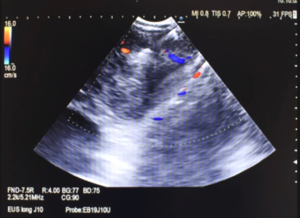

Step 2: the puncture (the first puncture will guide the rest of the process)

Based on our experience, we recommend that this procedure be performed by two operators. While a high skill bronchoscopist in EBUS-TBNA may be able to perform the technique after mastering the learning curve, we can ensure that having two operators makes the process easier, quicker, and safer. Sedation was performed with midazolam (0.07 mg·kg−1) and fentanyl citrate (0.5–2 µg·kg−1), starting with boluses of 1–3 mg of midazolam and 0.1 µg of fentanyl citrate. Sedation was maintained with intermittent boluses of 1.2 mg midazolam and 0.1 µg fentanyl citrate according to the clinical judgment of the pulmonologist. When viewing the ultrasound image, it is important to always use the Doppler mode to avoid any vessels (Figure 2A), carefully choose the location with the thinnest mucosa and lymph node capsule (Figure 2B), and steer clear of any cartilages before performing the TBNA (Figure 2C). The use of Doppler is essential in this procedure. Here we show a significant distance between the TBNA entry point and the lymph node capsule. This distance is due to the enlarged mucosa and cartilage, which should be avoided during the procedure (Figure 3A,3B).